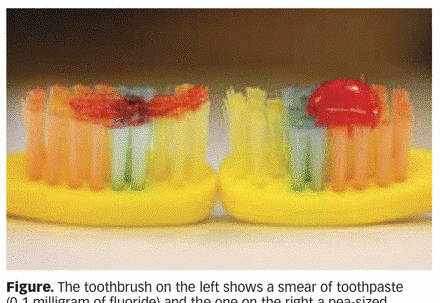

家长要在孩子第一颗乳牙刚露头就开始使用含氟牙膏帮助其刷牙,但用量需要严格控制。

每次不能超过薄薄一层或者大米粒大小(0.1g牙膏,约含0.1mg氟)(如下图-左)。每天早晚各刷一次,或遵照牙医或内科医生的医嘱。一定要确保牙膏的用量在正常范围内。

左图为3岁以下宝贝每次建议用量;

右图为3-6岁宝贝每次建议用量

• 对于3-6岁的宝贝

家长需要保证每次含氟牙膏的用量不超过豌豆大小(0.25g牙膏,约含0.25mg氟)(如上图-右)。每天早晚刷两次牙,或遵照牙医或内科医生的医嘱。在刷牙过程中密切观察宝贝,尽量减少牙膏的吞咽。